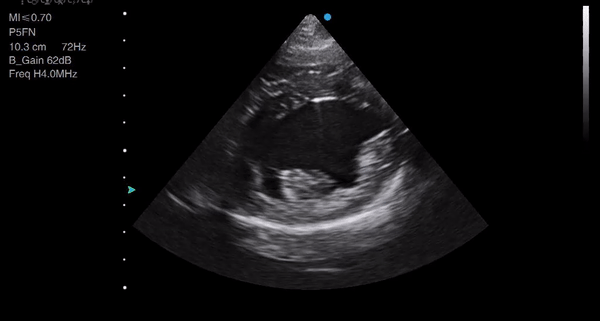

- Do you need to measure to tell which of these ventricles has increased wall thickness?

- Do you need an LA:Ao ratio to tell you which dog’s left atrium is dilated in the videos below?

3) Make subjective assessments

There is a lot of pressure to obtain measurements from echocardiograms, particularly an LA:Ao ratio (the ratio between the diameter of the aorta and the diameter of the left atrium, usually taken from the short-axis 2D image) in canine and feline patients and wall thickness in felines – two of the most difficult measurements to perform well!

Reporting measurements before you are confident with your imaging is inadvisable: firstly, because your measurements will have poor reproducibility and may be inaccurate; and secondly, because you need to train your own interpretation skills. Relying on measurements when you first start can absolve you from having to interpret the image yourself and can easily give false reassurance.